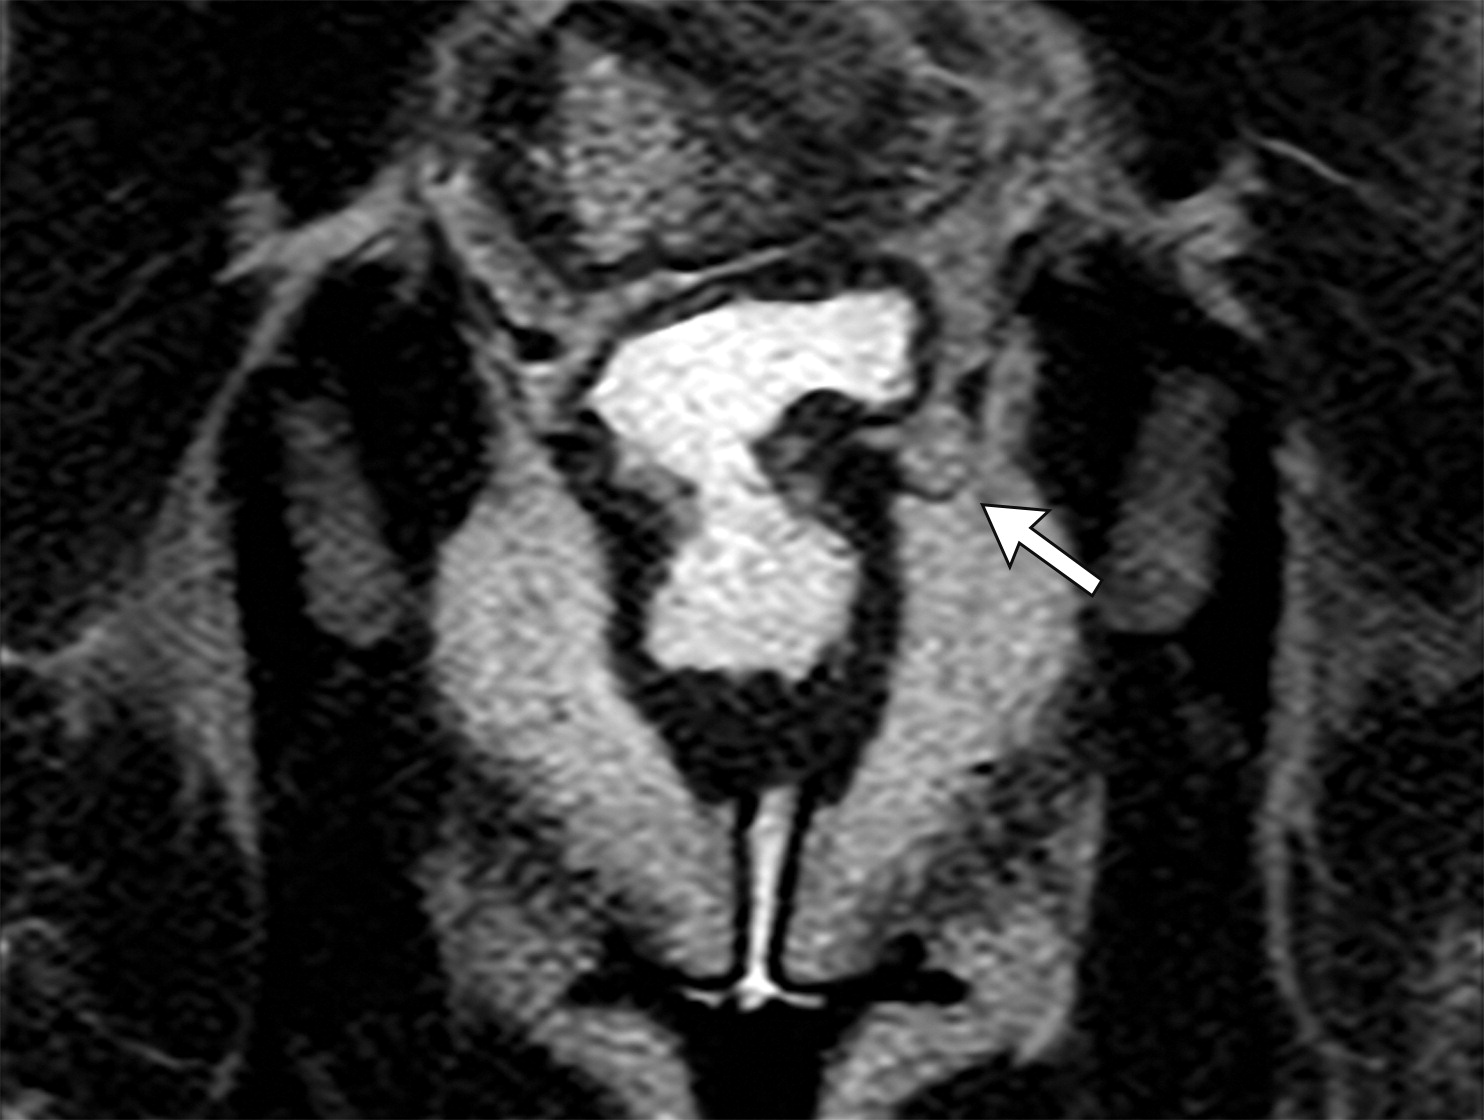

2e7c5baccf23e3a9e5963d9537af7b54.jpeg

马鞍袋征阳性。

膀胱右壁向后下垂(白色短箭头),这可能继发于Denonvillier筋膜的缺损。